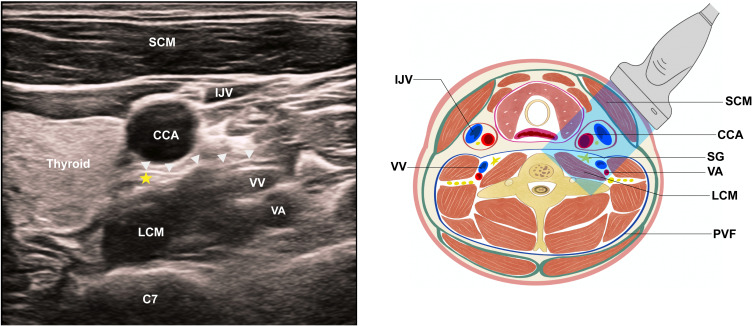

Methods: In this single-center, randomized, double-blind, placebo-controlled trial, 100 patients undergoing esophagectomy were randomly assigned to receive ultrasound-guided right-sided SGB with 7 mL of either 0.5% ropivacaine (SGB group) or normal saline (control group). The primary outcome was the incidence of POAF within 72 hours postoperatively. Secondary outcomes included the timing and duration of POAF, heart rate variability, other arrhythmias, sufentanil consumption, pain scores, vital signs, sleep quality, gastrointestinal recovery, length of hospital stay, complications and mortality.